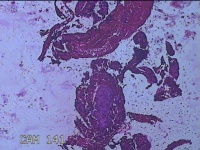

性别

女

年龄

46岁

临床诊断

异常子宫出血

一般病史

阴道流血伴血块6天。

标本名称

宫腔内组织

大体所见

灰白暗红色不规则碎组织2.5x2x0.7cm一堆。

图2